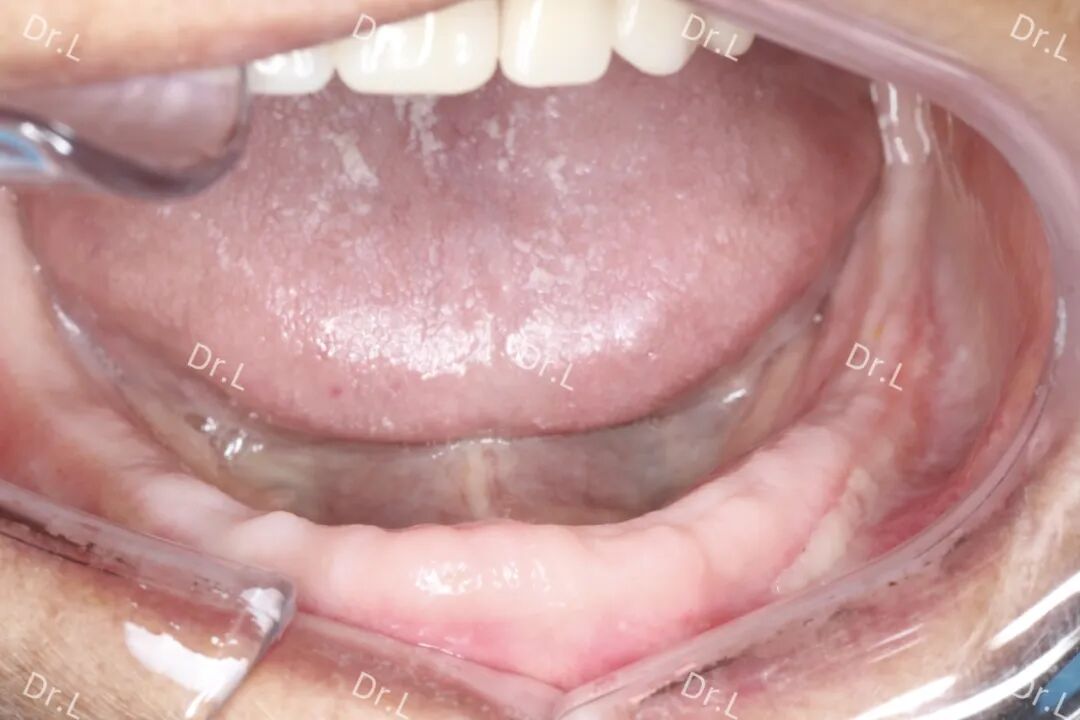

2023年年底,H爷爷怀着急迫的心情来到合山市人民医院口腔科,要求修复口内缺失牙。据悉,H爷爷因肿瘤放疗要求拔除了口内所有牙,现放疗暂告一段落,由于无牙对进食的影响颇大,他迫切想要制作一副假牙以方便进食。经口腔科医生详细检查后,发现H爷爷为全口无牙颌,下颌骨后牙区牙槽骨低平,中线不齐,长时间缺牙导致下颌骨习惯性前伸,肿瘤放化疗后口腔分泌唾液减少……采用普通全口义齿修复方式吸附力根本不能满足其正常咀嚼需求。